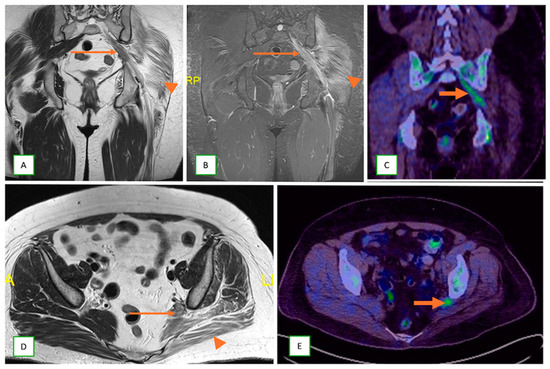

- Neurolymphomatosis describes intraneural spread of lymphoma and appears as diffuse enlargement of nerves, plexuses, spinal cord, and cauda equina. It shows more homogeneous enhancement than PNSTs and may be associated with lymphadenopathy or a known history of lymphoma [63] (Figure 20 and Figure 21).